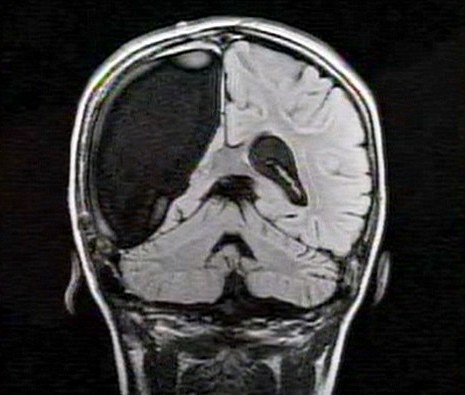

卡梅倫莫特在3歲那年患上一種被稱作大腦功能紊亂“拉斯穆森”綜合癥,這種病癥誘發(fā)患者的無序暴力行為和嚴(yán)重的癲癇。醫(yī)生建議,治療這種病癥只能通過嘗試消除引發(fā)此癥狀的大腦組織。而手術(shù)讓莫特失去了幾乎整個(gè)半邊的大腦。

據(jù)悉,莫特在手術(shù)后已經(jīng)可以跑動和玩耍,她在術(shù)后的第四周離開了醫(yī)院。醫(yī)生表示,雖然右半邊大腦的切除可能會給莫特帶來半身不遂的風(fēng)險(xiǎn),但孩子剩余的大腦仍具有很強(qiáng)的重組和布線能力。